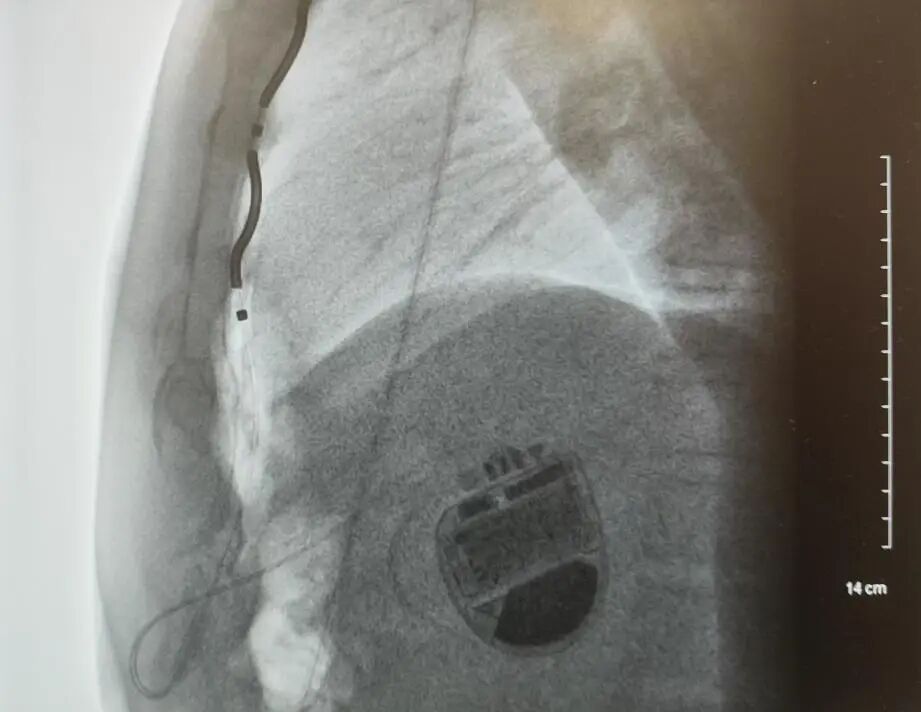

术中,蓝荣芳教授带领丰尚鹏教授凭借术前精准的CT评估,成功建立胸骨后隧道,一次性将电极放置于理想位置,胸骨下电极稳定,电学参数正常,除颤测试通过。患者在麻醉复苏后当即转回心内科普通病房,次日程控各项参数理想,显示除颤系统运作良好。